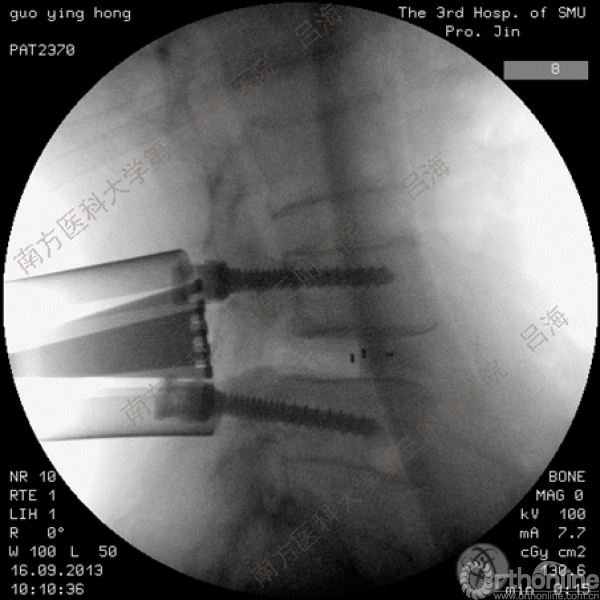

随着社会老龄化进程加快,胸腰椎退行性病变的治疗已经成为脊柱学术界的一个热点话题。MIS-TLIF手术可以治疗多种不同的胸腰椎退行性疾病,南方医科大学第三附属医院吕海教授结合病例为我们一一展示了该术式在治疗不同胸腰椎疾病时的具体手术过程。